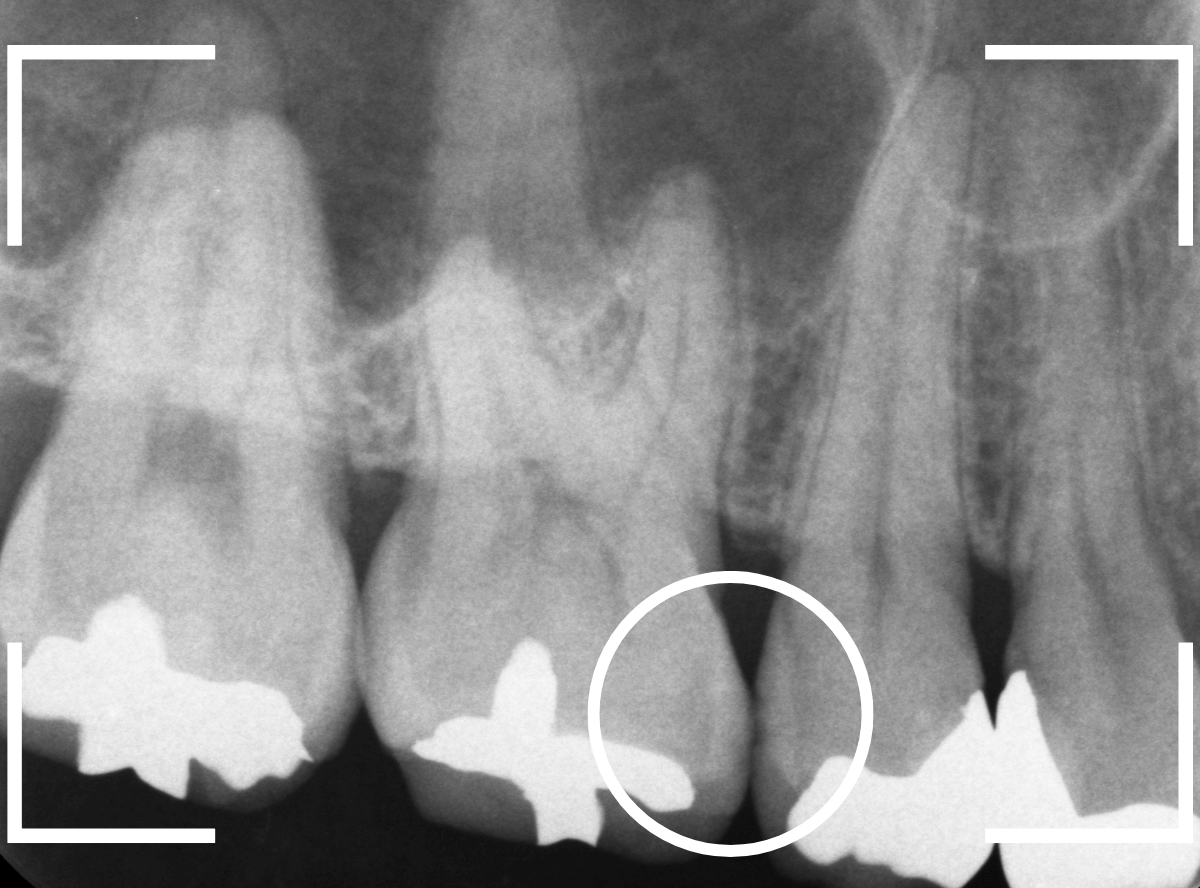

見た目に虫歯は見当たらず、痛みもありませんが、レントゲン写真で確認すると、歯と歯の間から、歯の神経まで達するほど虫歯が広がっています。

これほど大きな虫歯でも、症状がない事は多くあります。

検査時に〇部、歯と歯の間の小臼歯部に虫歯らしき黒い影があるのが見つかりました。

レントゲンでは後ろの大臼歯部の方が虫歯になっているように見え、小臼歯部は問題ないように見えます。